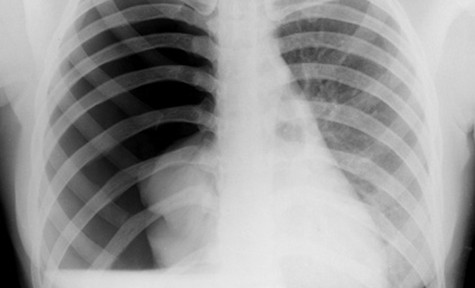

Chụp X-quang có thể giúp xác định chẩn đoán.

Click vào ảnh để xem 5 hình ảnh minh họa